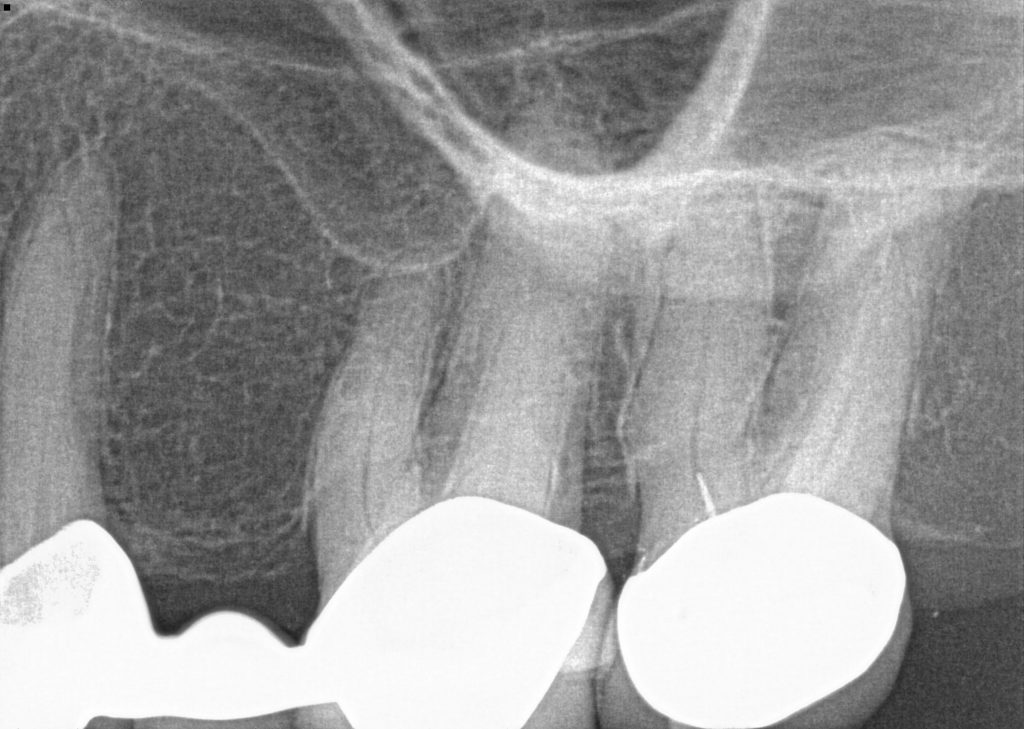

To grasp the gravity of a root canal failure, one must first apprehend what transpires during the procedure. A root canal involves the meticulous removal of infected or inflamed pulp from inside the tooth, followed by cleaning and disinfecting the interior before sealing it. This dental intervention aims to ease pain, preserve the tooth’s structure, and prevent further complications. However, the journey does not end once the procedure is complete; the tooth, though seemingly salvaged, remains vulnerable.

Though the success rate of root canals hovers around 85-95%, failure rates, albeit lower, are disconcertingly present. Complications may arise due to various factors: insufficient cleaning during the procedure; undetected fractures in the tooth; or even the ominous return of an infection. In these scenarios, the tooth may not only remain painful but act as a hollow chamber for bacteria, festering and multiplying silently.